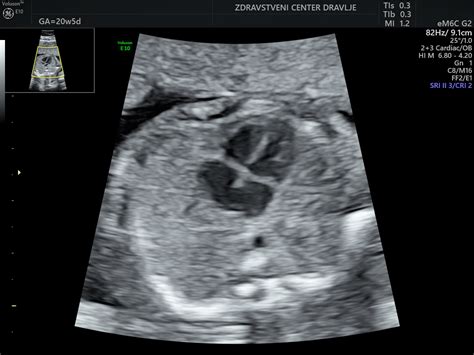

Skeletogram, ki prikazuje kosti hrbtenice, reber, nadlahtnice, podlahtnice in kosti prstov, omogoča zelo zanesljivo merjenje dolžin posameznih kosti. Vaginalni ultrazvok je v 15. tednu nosečnosti še vedno učinkovit, saj omogoča boljšo kakovost slike struktur v maternici zaradi majhne razdalje. V tem času se lahko že podrobno preučijo različni deli telesa ploda. Med 15. in 20. tednom nosečnosti je predviden pomemben pregled, imenovan "morfologija", kjer se podrobno preverijo različni deli telesa.